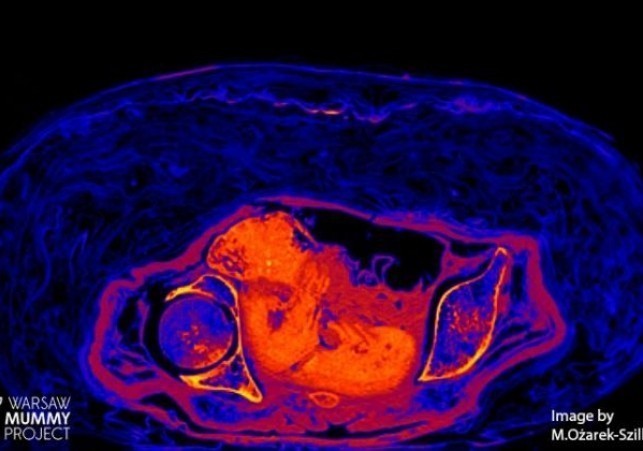

Płód znajdujący się w zmumifikowanej Egipcjance sprzed ponad dwóch tysięcy lat przetrwał do naszych czasów za sprawą bardzo nietypowego procesu rozkładu.…